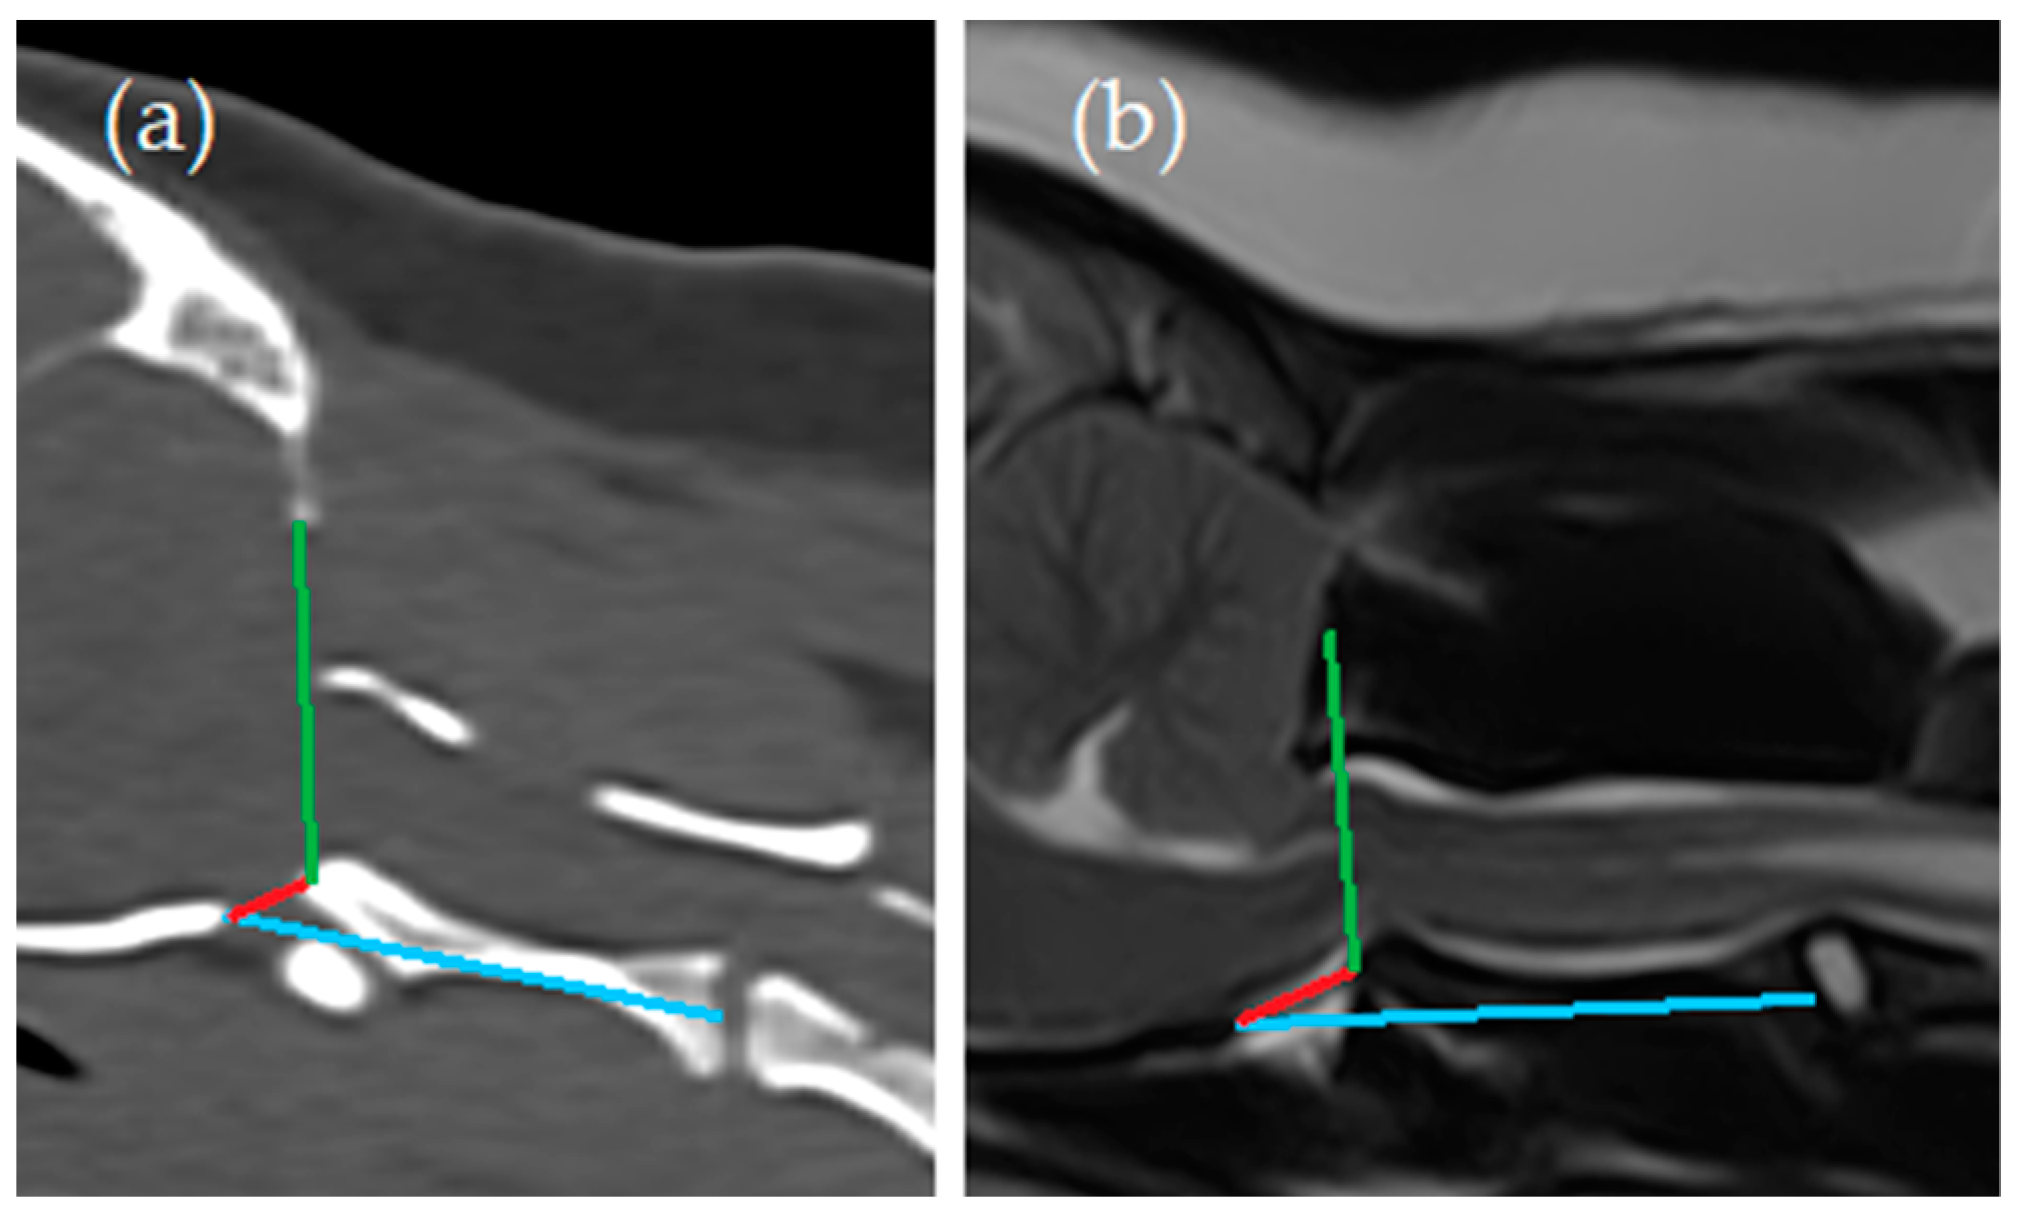

- Angle between the line from the caudal tip of the basioccipital bone to the cranial tip of the dens axis (red line) and the line from the ventral aspect of the supraoccipital bone to the cranial tip of the dens axis (green line) (Angle 1);

- Angle between the line from the caudal tip of the basioccipital bone to the cranial tip of the dens axis (red line) and the line from the caudal tip of the basioccipital bone to the midpoint of the caudal endplate of the axis (blue line) (Angle 2).